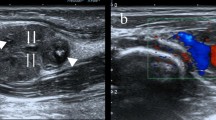

The concurrent surgical resection specimen showed papillary structures and variably sized cysts lined by cuboidal, columnar, and flattened cells (Fig. 5). Small nests of epithelial cells were also present within the stroma. The cytoplasm, which sometimes contained pigment granules or numerous vacuoles, was eosinophilic. Overall, the nuclei maintained a bland appearance, although occasional enlarged nuclei with prominent nucleoli were identified. Pigment-laden macrophages were present in some of the cysts. Mitotic figures were not identified. The stroma was quite vascular in some areas but in elsewhere was dense and sclerotic. Focally, the stroma immediately beneath the epithelium contained a slightly pleomorphic population of stromal cells with nuclei larger than those of the epithelial cells. These underlying cells did not stain positively for cytokeratin, whereas the surface epithelial cells were cytokeratin positive. All cells were negative for S-100 protein and GFAP. Estrogen and progesterone receptors were also negative. Additionally, immunostains for α-fetoprotein, chromogranin, desmin, epithelial membrane antigen, human chorionic gonadotropin, muscle-specific actin, neuron-specific enolase, placental alkaline phosphatase, and vimentin were negative. The cells also stained focally weakly with periodic acid-Schiff after diastase digestion. Review of the patient’s previous surgical material (1989) showed similar histologic findings (Fig. 6).

Previous surgical resection of endolymphatic sac tumor with similar histology to current tumor in Figure 5. (hematoxylin and eosin, 20 × ; inset, 40 ×).